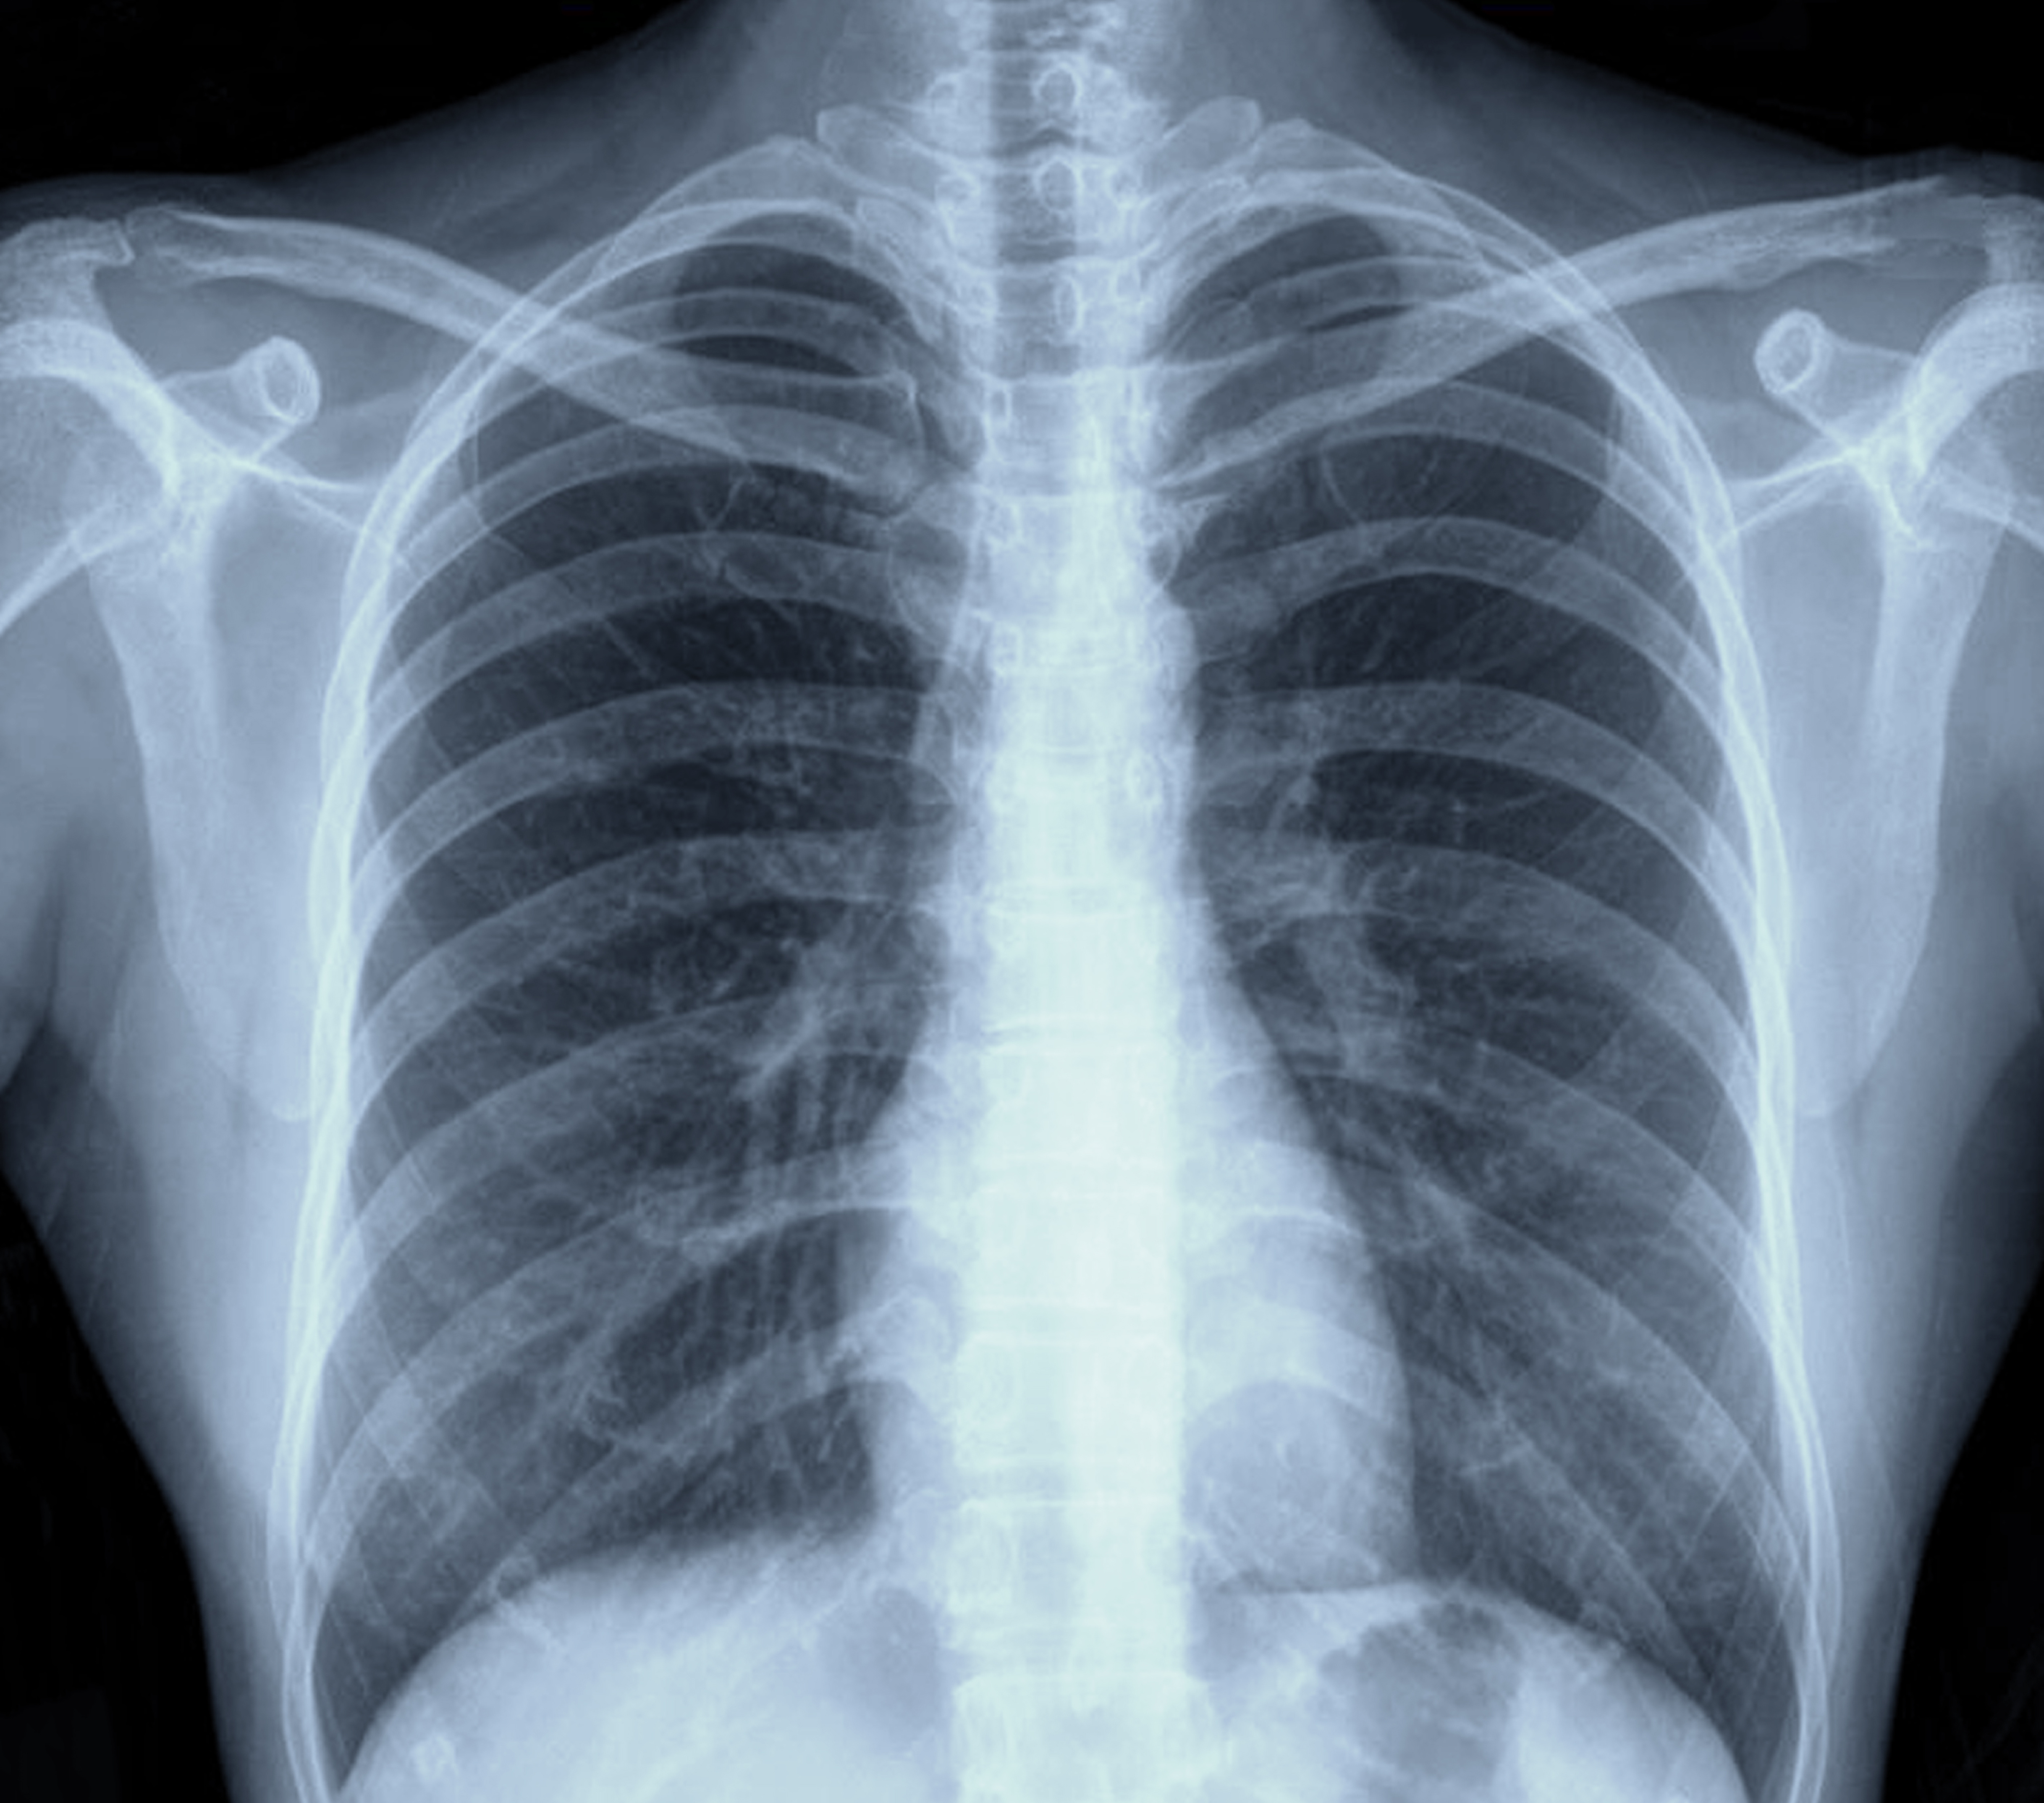

In an external validation data set for a deep learning bone-suppressed (DLBS) model, researchers found that adjunctive use of the DLBS model led to a nearly 15 percent increase in sensitivity for detecting pulmonary nodules on chest X-rays in comparison to radiologist assessment.